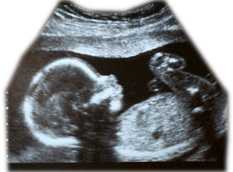

It is probable that many antipsychotics enter fetal circulation. Antipsychotics such as chlorpromazine, haloperidol and trifluoperazine have been in clinical use for several decades, but there is little compelling evidence of an association between their use and birth abnormalities.

Use of an antipsychotic in the latter stages of pregnancy can lead to the development of extrapyramidal side effects1 in the newborn as well as withdrawal effects (agitation, hypertonia, hypotonia, tremor, somnolence, respiratory difficulty, and feeding problems). Newborn infants might also display antipsychotic side effects such as lethargy, tremor, paradoxical hyperexcitability—and they may have low apgar score2.

The antipsychotic dose and its duration of use determine the level of exposure of the fetus to the drug.

Before starting an antipsychotic in a woman of childbearing age, it is valuable to discuss possible effects on fertility and options for birth control. Antipsychotic treatment should be reviewed in women considering starting a family, carefully considering the benefit and risk of continuing antipsychotic treatment. If possible, an antipsychotic, especially prolonged-acting (‘depot’) injection, should be avoided during pregnancy. Women should be advised to discuss their antipsychotic treatment if they discover they might be pregnant.

Neonates born to a mother taking an antipsychotic should be carefully monitored for antipsychotic effects including extrapyramidal side effects and withdrawal effects. Any difficulty with breathing and feeding should be addressed.